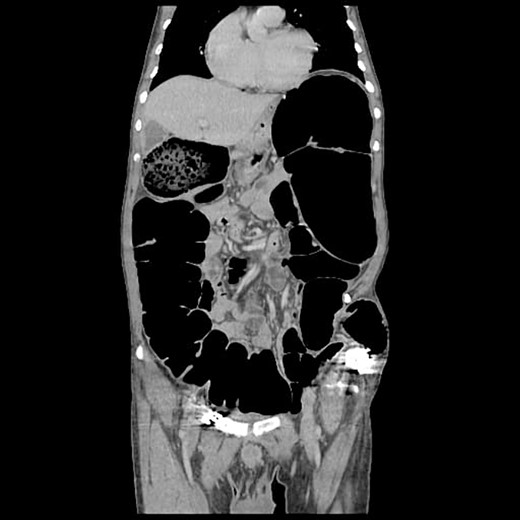

The CT abdomen pelvis (Figs 5 and 6) showed signs of bowel obstruction signs, along with an internal hernia at the place of the prior ORIF surgery. These findings were thought to be the core cause of the patient’s presentation in align with the taken history, physical examination of the patient.

The preferred imaging method is computed tomography. While ultrasound is a low-cost, low-risk alternative for assessing these hernias, it does not reveal concomitant abdominal illness and is used less frequently in clinical settings [22, 23]. Conventional X-rays revealed dilated bowel segments. The computed tomography (CT) picture indicated several dilated colonic segments as well as a hernial defect on the left side of the abdomen. Moreover, ultrasonography of the abdomen and pelvis revealed a moderate reactive free fluid accumulation in the pelvis and a bowel loop imprisoned in the apparent bulge.